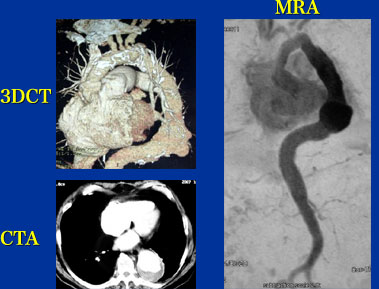

78歳 男性

検査異常(TAA弓部置換後)

【起始・経過】

TAAの診断で、2002年他院にて弓部置換術を施行。2006年のCTで置換した人工血管の末梢側に径6cmの動脈瘤を認めた。2007年のCTで8cmと増大傾向であるため当院紹介となった。CT上左鎖骨下動脈狭窄も疑われた。

【既往歴】

慢性心不全 SAS 腎機能低下(Cr 1.8)

高血圧(+) 糖尿病(ー) 喫煙歴(+)

【治療計画】

Gore TAG stent

左鎖骨下動脈 stent

症例7,8